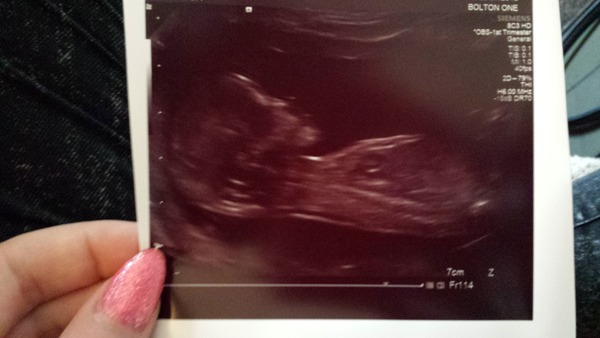

CubanoHabana · 22/07/2015 15:37

Posted on end of last thread without realising new thread is here! been mia due to work/hospital stay/bleeding but all is fine. Sorry if I've missed things, hope everyone is doing well.

12 week scan went well, will try to post pic

CubanoHabana · 22/07/2015 15:38

Any idea on blue/pink?

No idea cubano but a cute nose! Glad all is well with you.

Cute picture Cubano I'm gonna guess pink due to what kinda looks like a horizontal nub. Smile

Welcome back cubano glad all is well .. Girl! Im guesing Grin